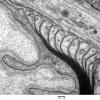

PERIPHERAL NEUROPATHY

3 NORMAL MYELIN & SCHWANN CELLS